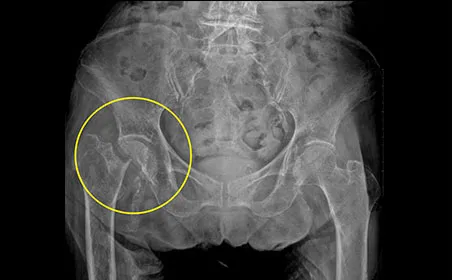

고관절 질환 3. 대퇴골두 무혈성 괴사증

소켓 모양의 고관절에 맞물리는 둥근 모양의 대퇴골두가 혈액 순환 문제로 뼈 조직이 괴사하는 질환이며, 대퇴골두 무혈성 괴사가 주요 원인입니다. 주로 30~50대에 나타나며, 남성의 발병률이 여성보다 높습니다. 약 60%가 양측성으로 나타나고, 주된 원인은 기저 질환으로 인한 코르티코스테로이드의 장기 사용과 과도한 알코올 섭취로, 전체 사례의 약 90%를 차지합니다.